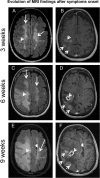

We present two natalizumab-treated multiple sclerosis patients who developed glioblastoma multiforme (GBM) with variable outcomes. One patient had an isocitrate dehydrogenase (IDH)-wildtype GBM with aggressive behavior, who declined treatment and died 13 weeks after symptoms onset. The other patient underwent resection of an IDH-mutant secondary GBM that arose from a previously diagnosed grade II astrocytoma. He is still alive 5 years after the diagnosis of GBM. JC virus was not detected in either case. Whether natalizumab played a role in the development of GBM in those patients deserves further investigation.